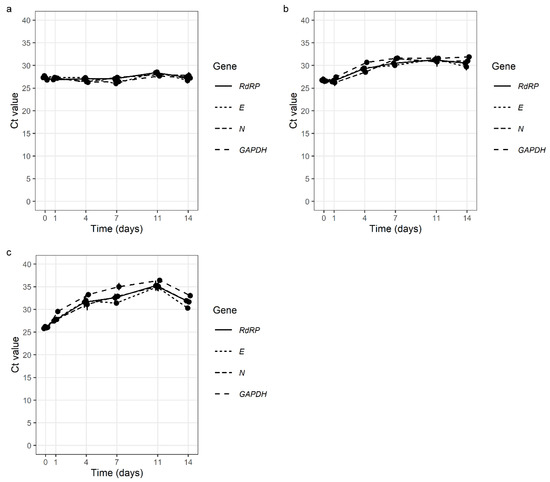

Autoimmunity and Immunodeficiency in Severe SARS-CoV-2 Infection and Prolonged COVID-19.

Current Issues in Molecular Biology.

2022,

45(1),

33-50,

ISSN: 1467-3037,

PMID: 36661489,